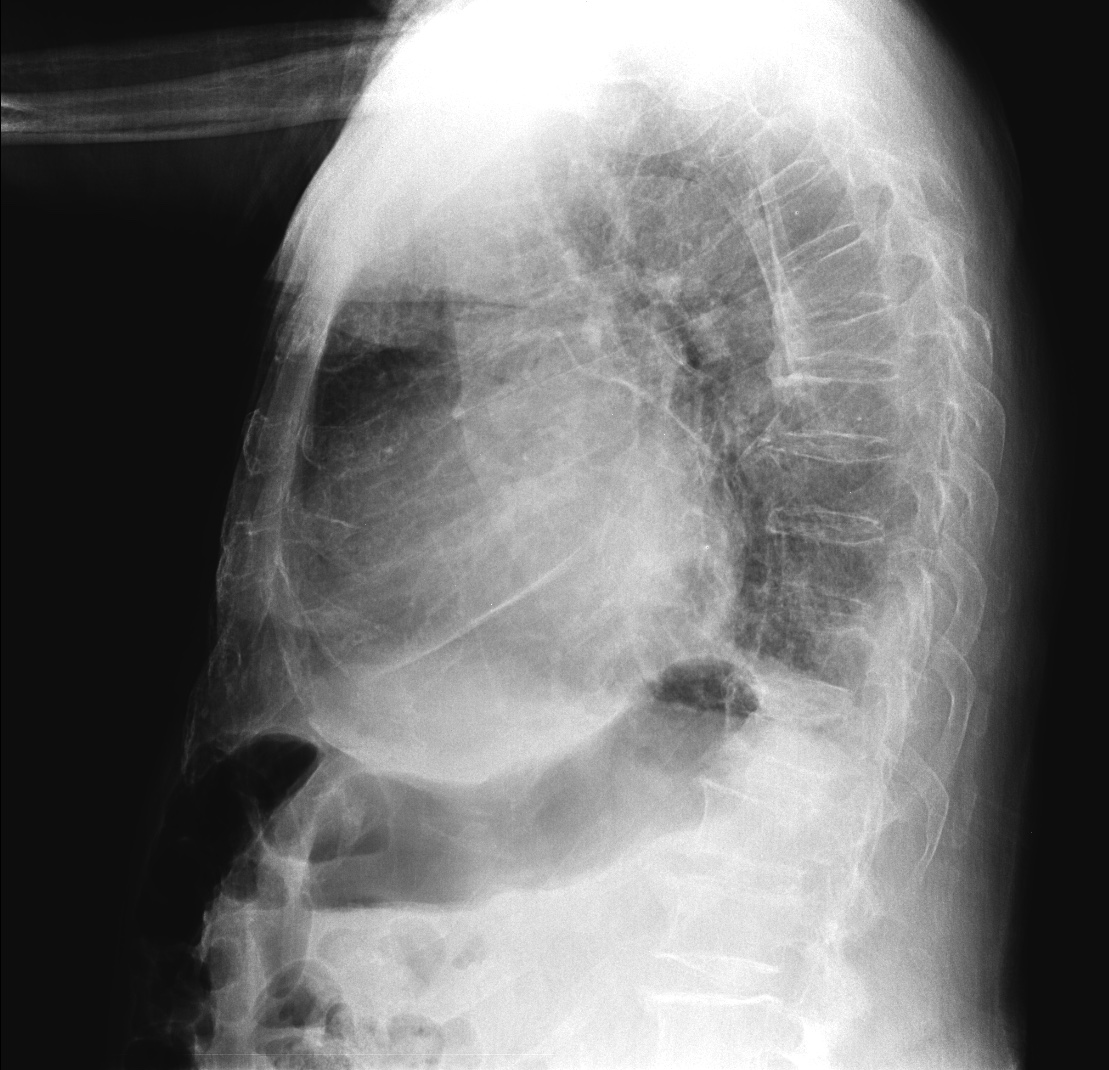

CASO: Febrícula y tos de 4 días de evolución.

Hallazgos:

- En la placa PA se observa una asimetría en los hilios pulmonares, el hilio izquierdo tiene una densidad aumentada.

- Tras examinar la placa lateral se observa un aumento de densidad en la columna que puede ser compatible con una condensación, es el signo de la desnificación vertebral.

SIGNO DE LA DENSIFICACIÓN VERTEBRAL: En la radiografía lateral normal, la densidad de la columna torácica tiende a disminuir desde la parte superior hasta el diafragma; la alteración de ese patrón por la presencia de una densidad superpuesta a la columna, indica la existencia de una consolidación pulmonar. Este signo adquiere especial valor cuando en la proyección posteroanterior la consolidación está oculta en el espacio retrocardíaco o en la base pulmonar.